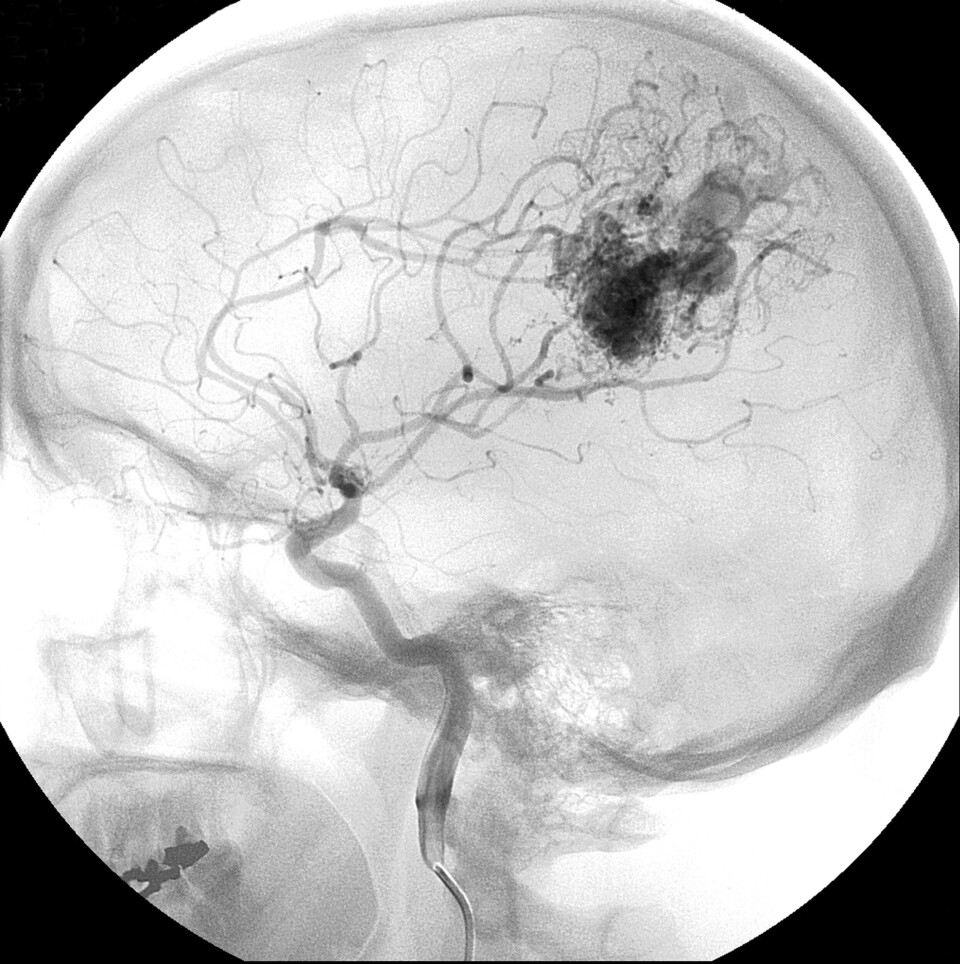

I løpet av de aller første timene fra symptomene oppstår, må pasienten undersøkes med en røntgenmaskin – CT-skanner – og vurderes av sykehuslege som kan gi akuttbehandling.

Et akutt hjerneslag er en plutselig oppstått reduksjon av blodtilførselen til en del av hjernevevet. Slik skade fører til redusert aktivitet i det rammede området, og dermed plutselig tap av funksjon.